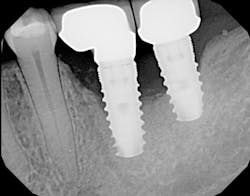

The most critical aspect of any implant system is the interface between the implant fixture and its surrounding bone (figures 1-5). Integration between the fixture and its surrounding bone is the foundation of modern implant dentistry. There is little we can do to modulate bone healing, but we can modify the implant fixture itself.

Figures 1-5: Figures 1 through 4 illustrate, respectively, a seven-year follow-up visit and a three-year follow-up visit of two different implant systems. Implant No. 22 (figure 5) shows peri-implant radiolucency following functional loading, indicating fibroencapsulation and loss of integration into bone, necessitating removal.